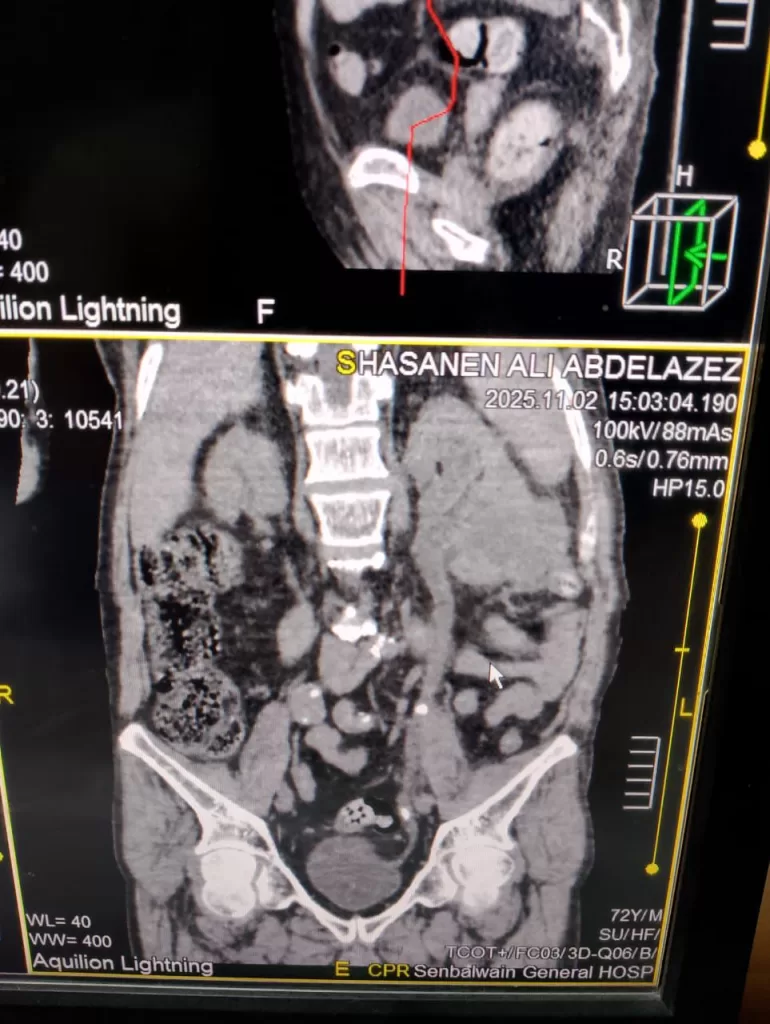

وأوضحت المستشفى أنه بعد إجراء الأشعة المقطعية بدون صبغة على المسالك البولية، تبين وجود حصوتين بالحالب الأيسر وارتجاع على الكلية اليسرى والتهاب بالكلية، مما استدعى التدخل الجراحي الفوري.